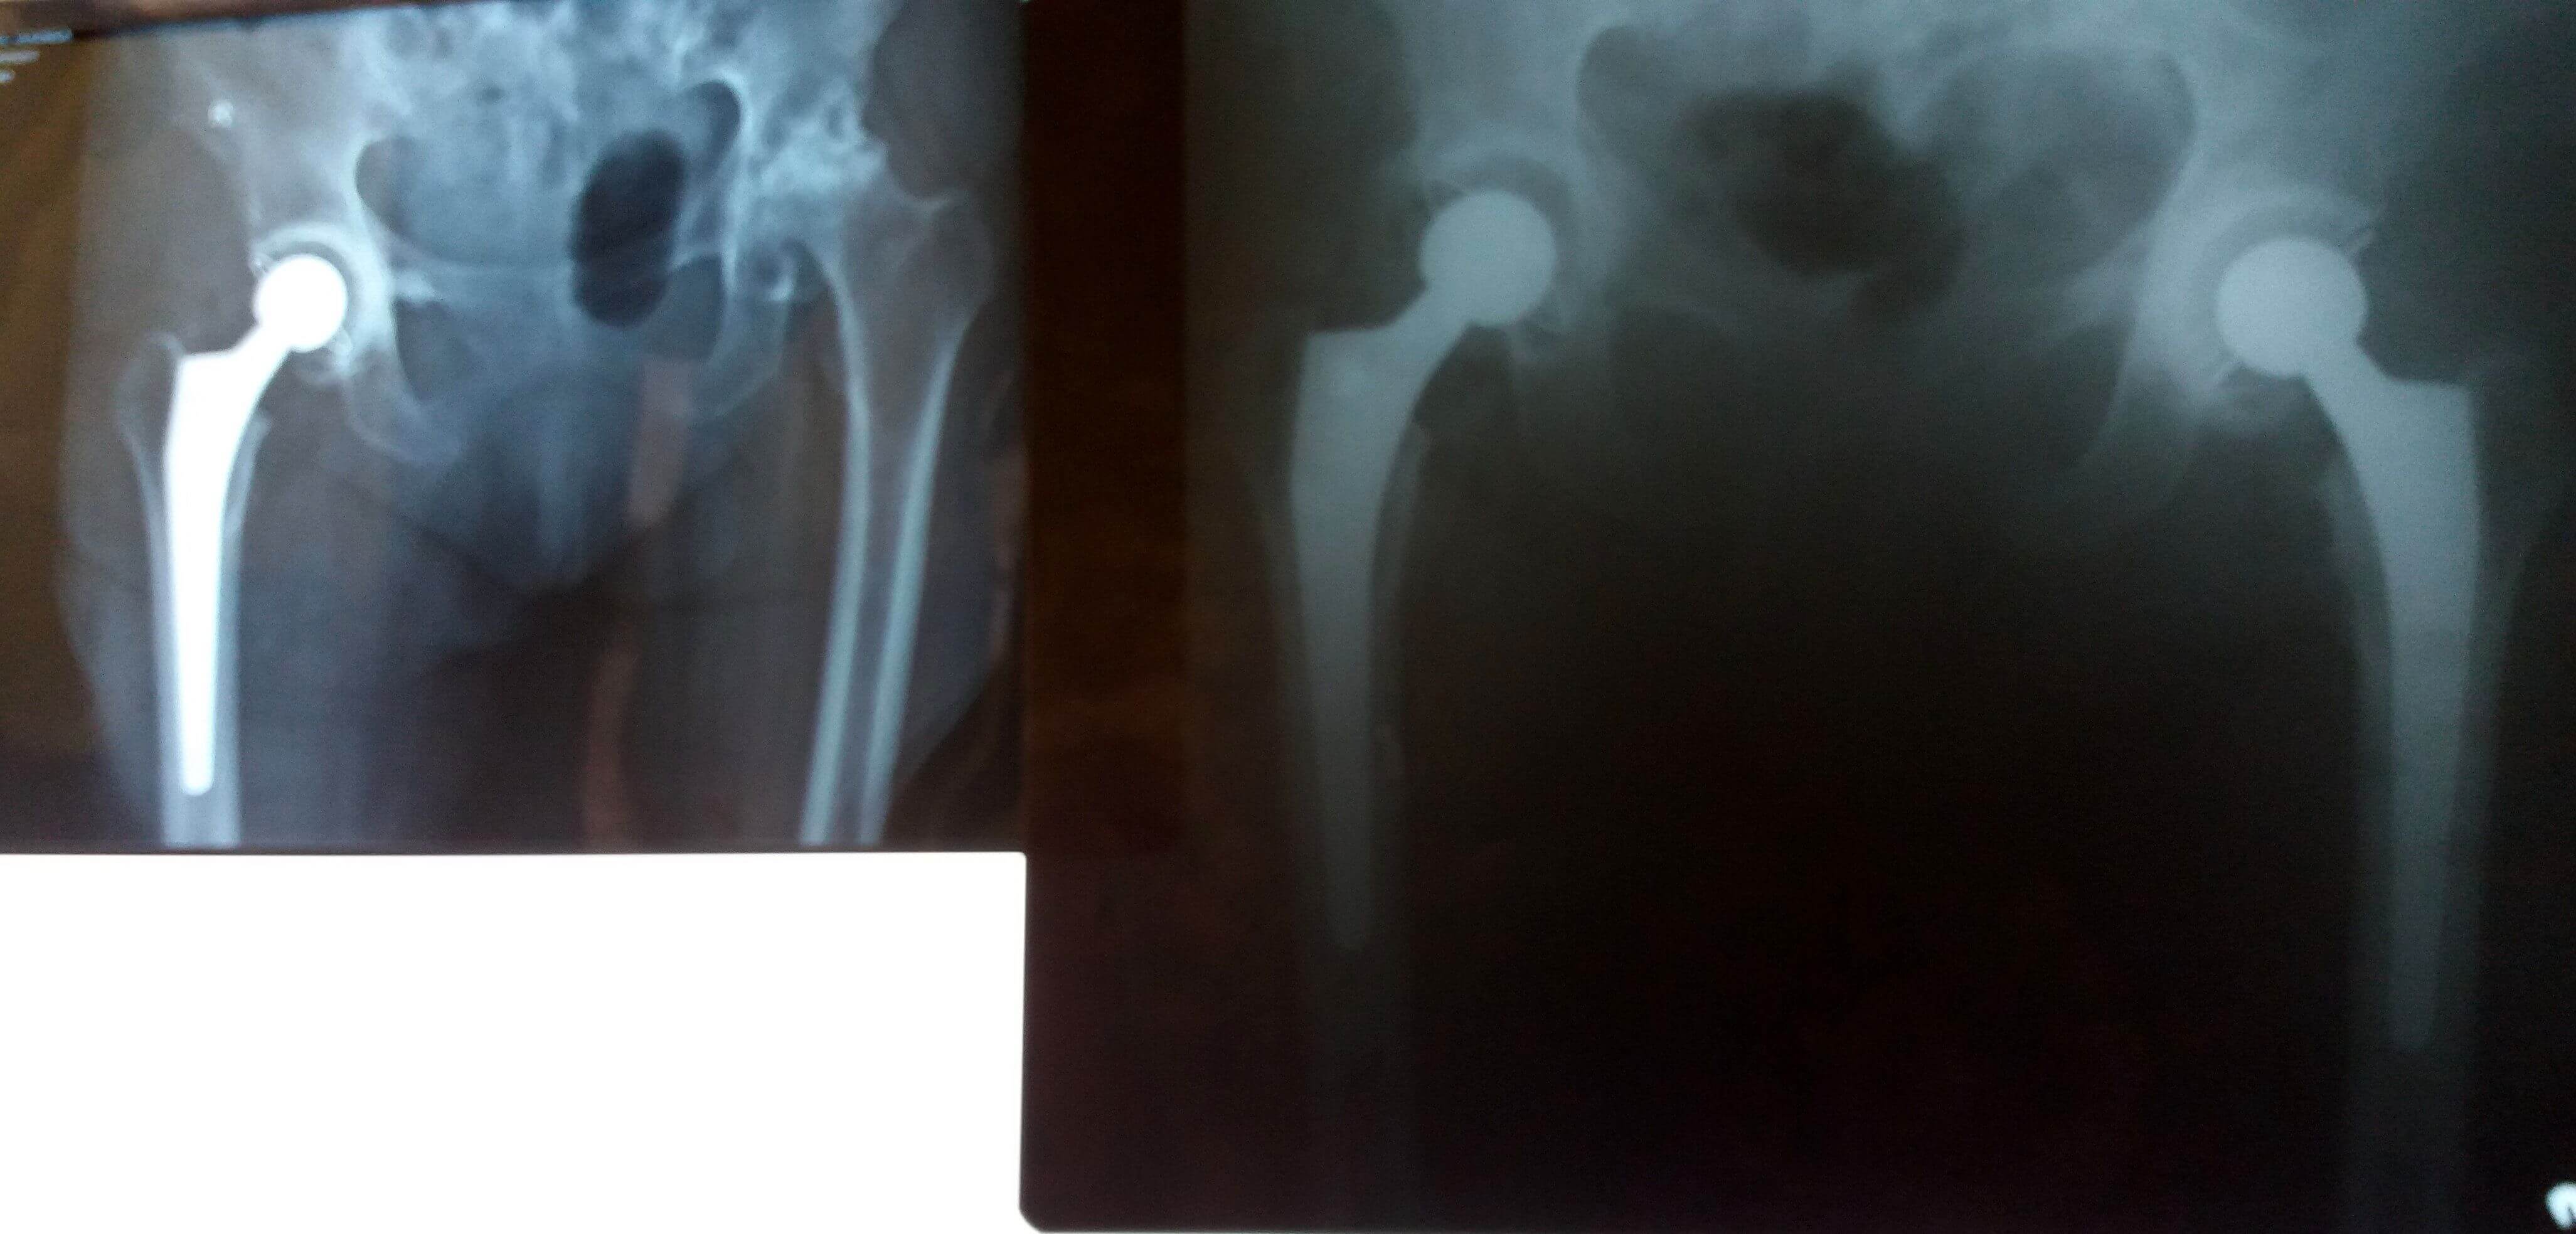

Medicii secției Ortopedie-Traumatologie din cadrul Spitalului Clinic Județean de Urgență “Sf. Apostol Andrei” Constanța au efectuat în premieră, mai multe intervenții minim invazive cu abord anterior pentru proteza de șold.

Abordul minim invaziv practicat în artroplastia totală de şold este o intervenție mai eficientă față de abordul clasic, sângerarea minimă și păstrarea intactă a mușchilor (nu sunt secționați) fiind câteva dintre avantajele care duc la o recuperare rapidă și, implicit, o perioadă redusă de spitalizare.

Până acum la SCJU “Sf. Apostol Andrei” Constanța au fost efectuate 4 intervenții de acest gen, ultimul pacient fiind o femeie în vârstă de 75 de ani căreia i-au fost montate 2 proteze de șold în cadrul aceleiași internări, perioada de spitalizare fiind de maximum 10 zile. Intervențiile minim invazive cu abord anterior pentru proteza de șold sunt efectuate la SCJU, în momentul de față, doar de către dr. Băjenescu Titi Marian și dr. Alexandru Șerban, medicul șef al secției Ortopedie-Traumatologie.